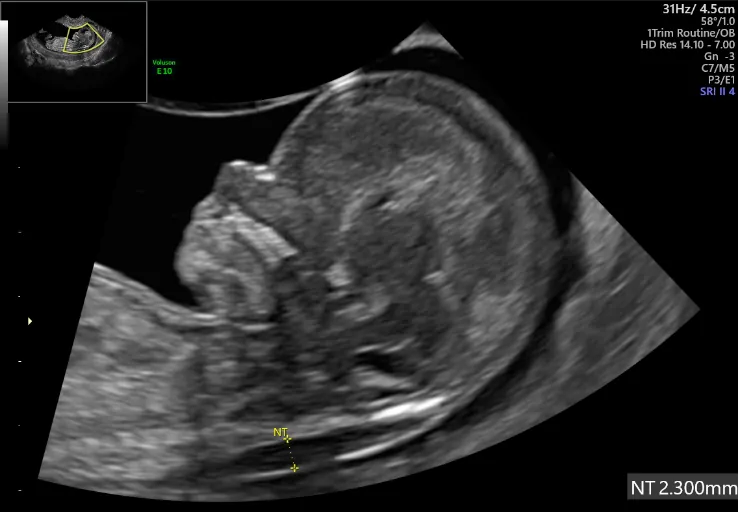

④胎児ドッグ(胎児初期精密超音波検査)(費用25,000円~50,000円)

妊娠12~13週に行います。

超音波検査で、NT(Nuchal translucency)首の後ろの透明な部分、鼻骨、心織の弁血流、静脈管血流、顔貌(耳介の位置や類の形成など)を総合的に評価する事ができます。また、Fetal medicine foundationのシステムを使う事により13トリソミー、18トリソミー、21トリソミーの確率評価を出す事が可能です。

染色体異常症の検査だけではなく、心臓や脳、手指などを観察できる事が利点ですので、疾患を知りたい方は良いでしょう。

21トリソミーの場合、検出率は90%と言われています。

※検出率とは、21トリソミーの赤ちゃんが、この検査を受けて検査陽性となる率です。

NTには正常値の設定はありません。一般的には3mm以上を厚いと判断しますが、3mm以上あっても異常の確率が3mm以下に比べると高くなるという意味です。正確には、赤ちゃんの大きさに対しての比率となります。

NTが厚い場合、染色体異常症や心疾患との関連があります。赤ちゃんの評価はNTだけではありません。総合的な判断となります。

NT計測にはFetal medicine foundationでのテストに合格しライセンスを取得した医師、または専門スタッフの計測が望まれます。